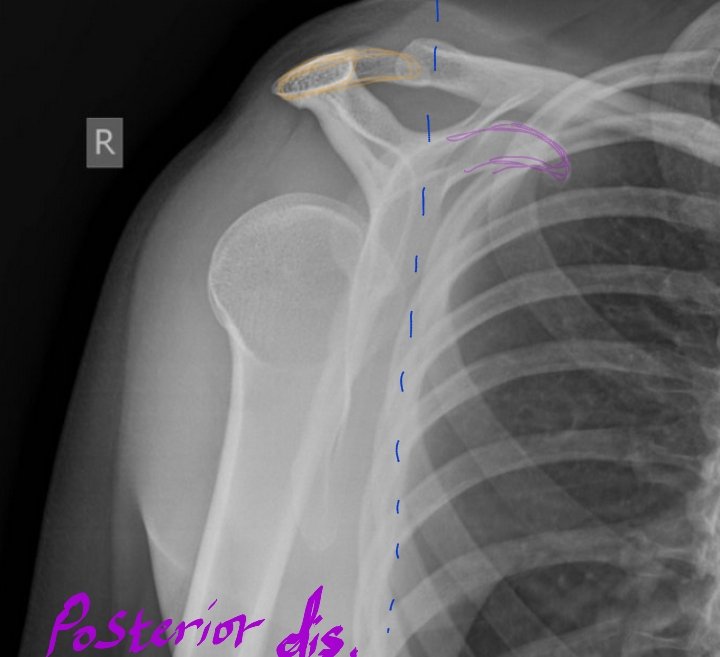

Scapular Y view lateral (Anterior Oblique position of shoulder)

•الخلع:هو خروج عظمة الذراع من مكانها الطبيعي لتتحرك نحو الأمام(وهو الأكثر حدوثاً)أو الخلف(أقل حدوثاً).

ويتم تقييم النوع من خلال موقع

Head of humerus

في حالات الخلع(الأمامي):

(Anterior dislocation)

Humeral head will be inferior to coracoid process.

الخلع الخلفي:

(Posterior dislocation)

Humeral head will be inferior to acromion process.

لاحظ موقع humeral head

بالنسبة لل

Acromion(orange) and Coracoid(violet)